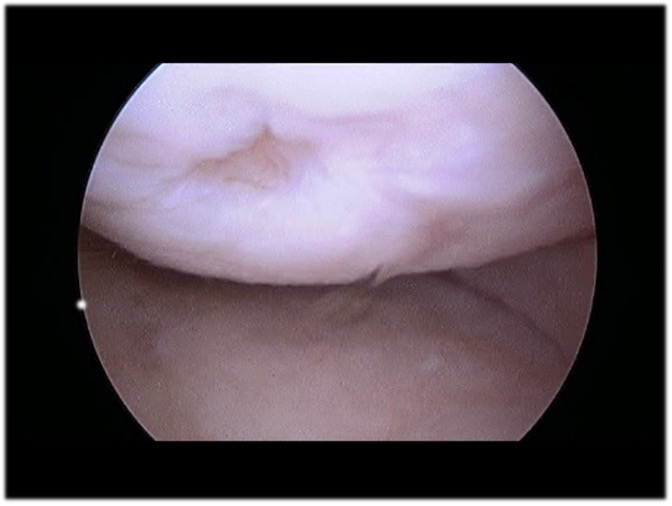

Articular Cartilage Defects of Knee Knee & Sports Orthobullets Knee Cartilage Defect Knee cartilage is tissue that lines the ends of the bones in the knee joint, and its job is to make the knee bones glide over each other smoothly when we bend and straighten the knee. Cartilage loss in the knee can lead to complications like bone spurs, cysts, and lesions. Cartilage damage is most frequently seen between the ages. Knee Cartilage Defect.

From www.researchgate.net